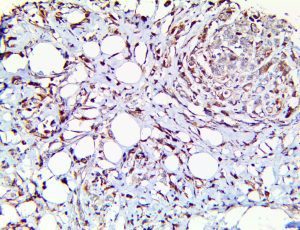

Clinical and laboratory manifestations of HLH include fever, enlarged liver and/or spleen, neurologic dysfunction, coagulopathy, liver dysfunction, cytopenias (i.e., low levels of erythrocytes, leukocytes, and/or platelets), hypertriglyceridemia, hyperferritinemia, hemophagocytosis, and eventually diminished NK cell activity as the immune system becomes progressively paralyzed. HLH can be familial (primary HLH) or secondary to another disease process (sHLH), such as rheumatic disease, in which it is referred to as macrophage activation syndrome (MAS, characterized by elevated ferritin).

This activation induces inflammatory monocytes to highly express IL-6, starting a localized and then systemic cascade effect that results in hyperproduction of IL-6, which accelerates the inflammatory process. Because IL-6 also increases vascular permeability, excessive levels cause blood vessels to become very leaky. This, along with clotting factors released from vascular endothelial cells, stimulates the coagulation cascade, resulting in microthrombosis (tiny clots), which leads to ischemia and tissue death of the kidney, intestines, heart, liver, brain and extremities.